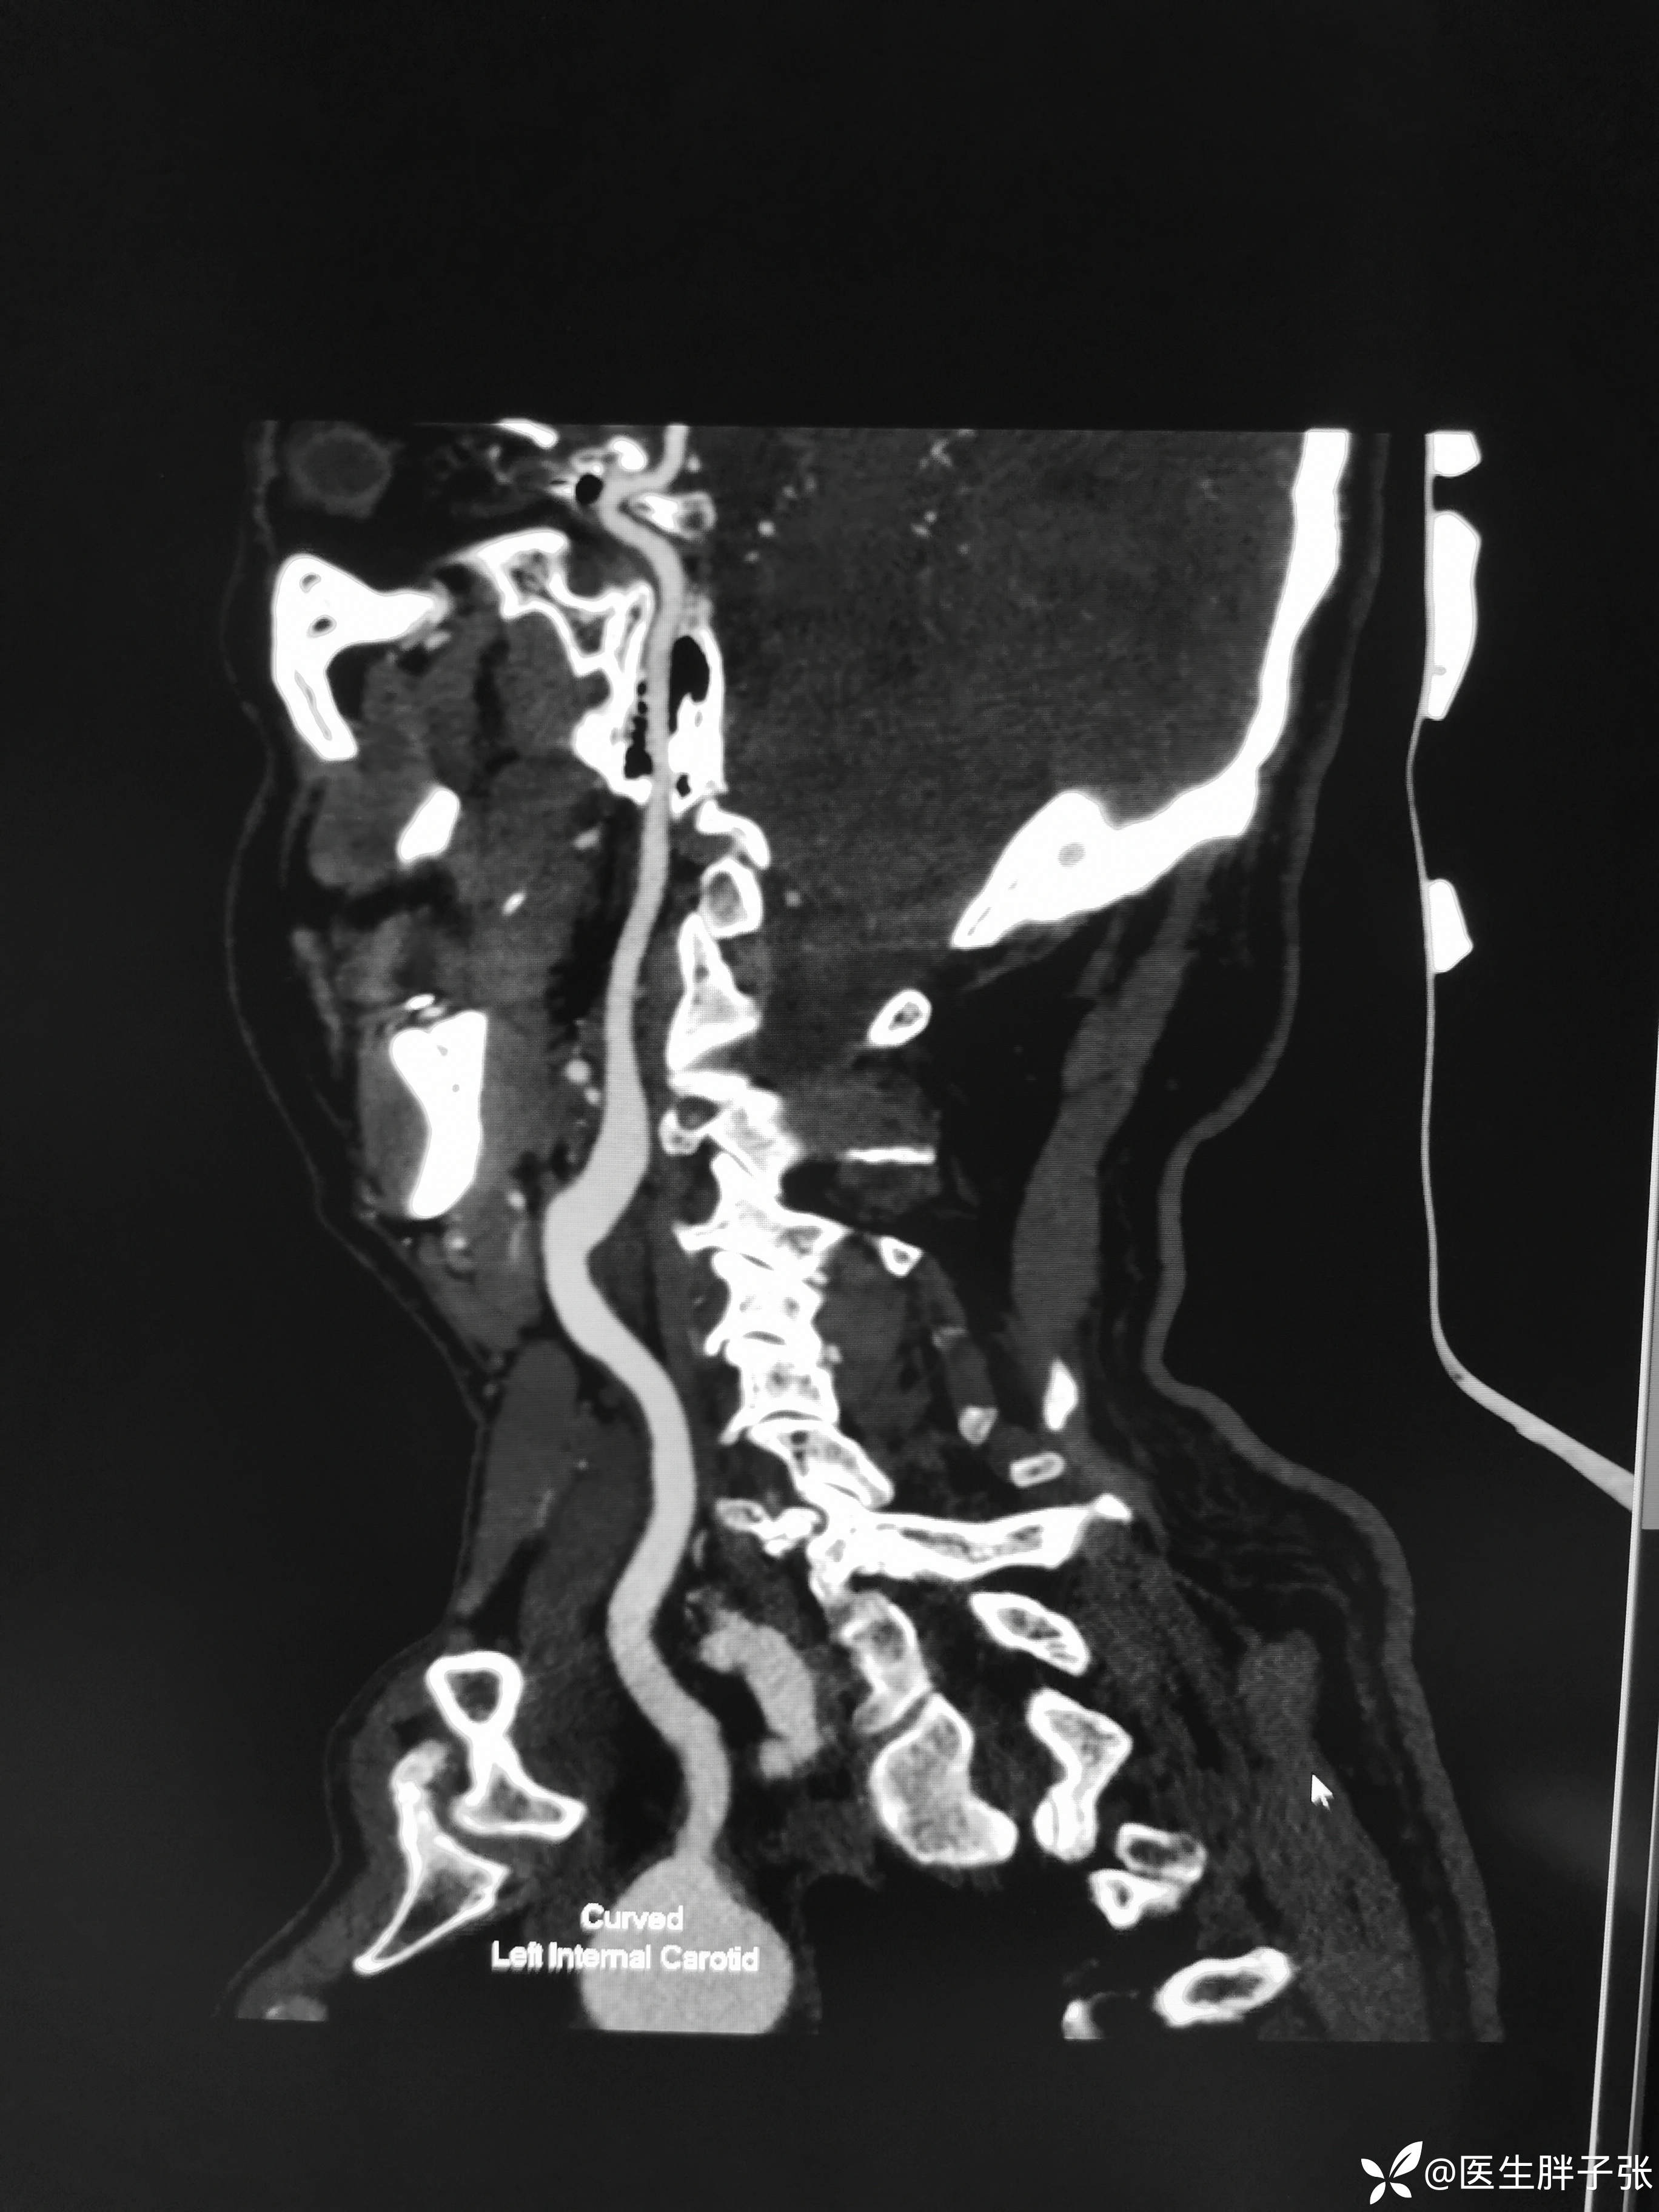

头颈部CTA提示左侧椎动脉闭塞、右侧椎动脉开口中度狭窄、左侧颈内动脉动脉瘤。